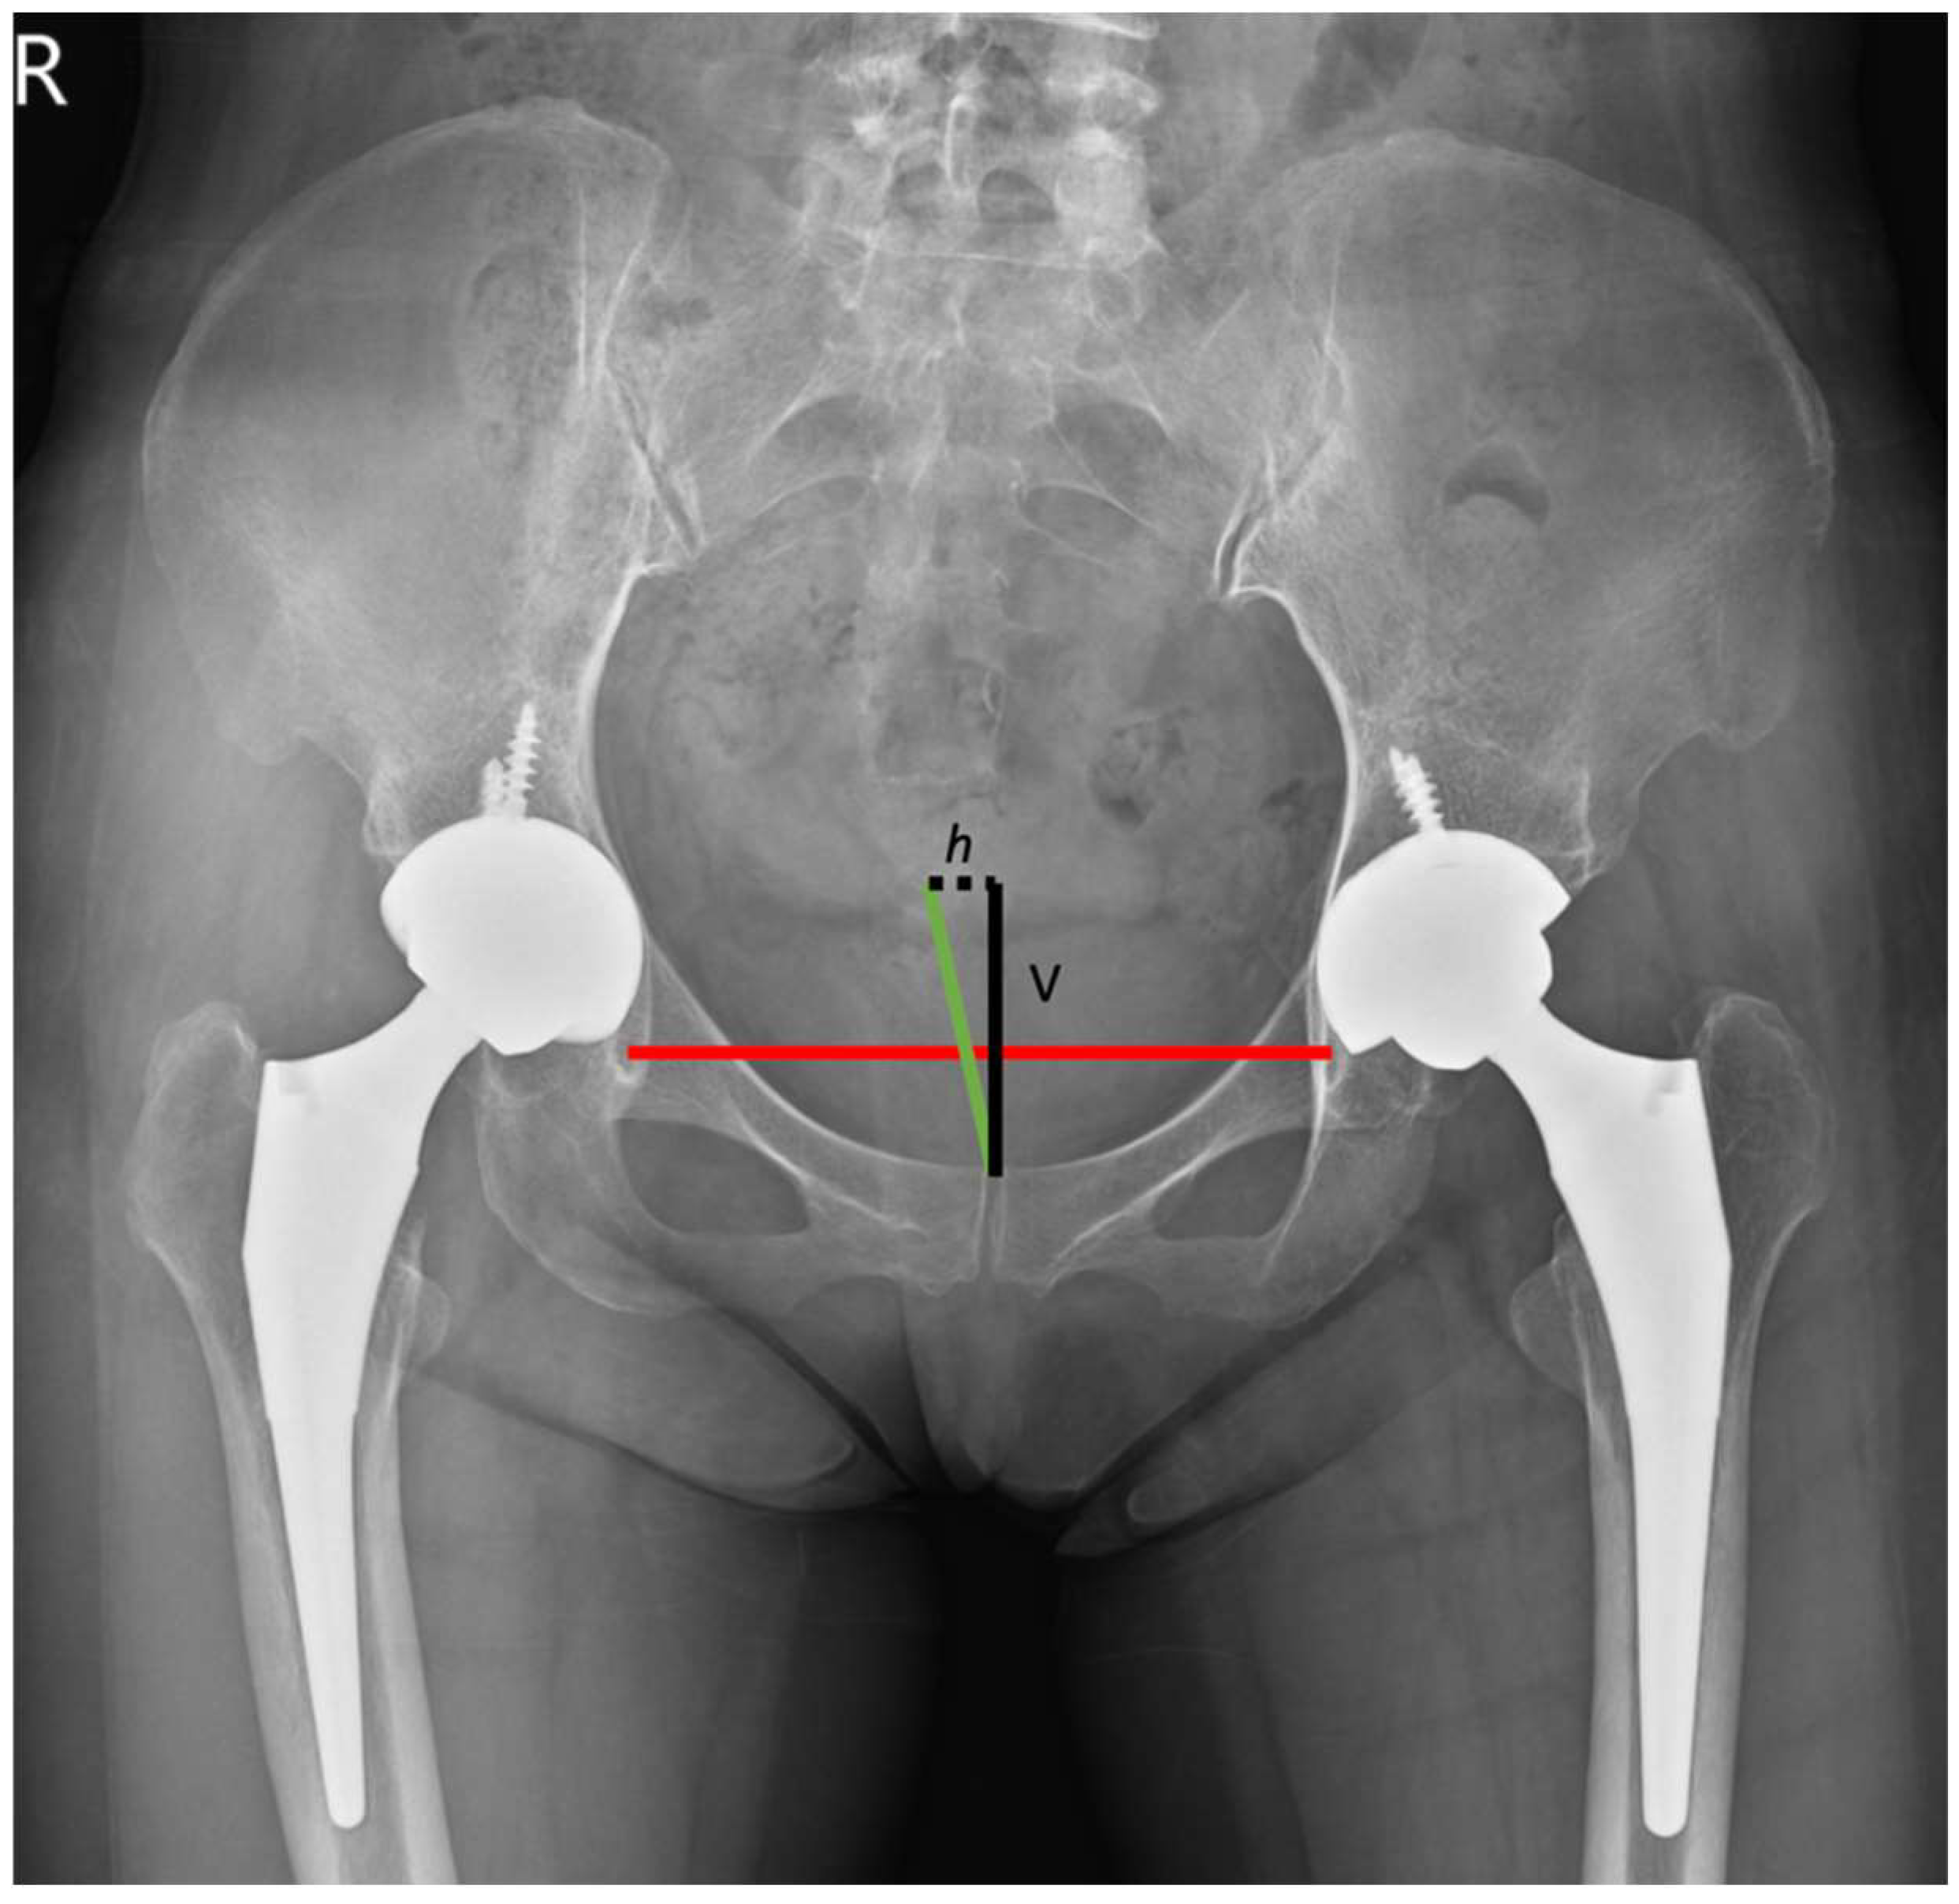

From www.cortho.org

Leg Length Discrepancy After Hip Replacement Complete Orthopedics Hip Replacement Test hip replacement can address hip pain and stiffness for people with arthritis, avascular necrosis or other forms of hip joint damage. The hip is one of the body's largest joints. The socket is formed by the acetabulum,. During a hip replacement surgery, an orthopaedic surgeon replaces both ends or one end of the damaged hip joint with artificial parts.. Hip Replacement Test.

From www.mdpi.com

JCM Free FullText Degree of Pelvic Rotation in the Coronal Plane Hip Replacement Test The hip is one of the body's largest joints. if you're considering hip replacement surgery, here are some things that can help you decide if it's right for you. The socket is formed by the acetabulum,. hip replacement surgery is a procedure in which a doctor surgically removes a painful hip joint and replaces. hip replacement can. Hip Replacement Test.